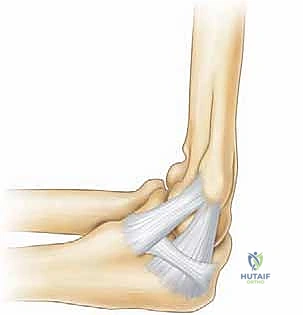

يوفر التكوين العظمي لمفصل الكوع (خاصة المفصل العضدي الزندي) استقرارًا أساسيًا لقوى الانقلاب (Valgus) والتقوس (Varus) بشكل رئيسي عند أقصى نطاقات الحركة: تحديدًا عند زوايا أقل من 20 درجة من الثني (شبه مفرود)، وأكبر من 120 درجة من الثني (مثني بشدة).

ومع ذلك، فإن النطاق الحاسم لمعظم الأنشطة الرياضية، وخاصة الرمي، يقع في القوس الحركي بين 20 و 120 درجة من الثني. في هذا القوس الوظيفي الحرج، تعتبر الأنسجة الرخوة (الأربطة والعضلات) هي المثبتات الرئيسية للمفصل، وليس العظام.

وهذا هو السبب في أن سلامة الرباط الجانبي الزندي (UCL) أمر بالغ الأهمية. يتكون هذا الرباط من حزم أمامية وخلفية ومستعرضة، وتعتبر الحزمة الأمامية هي خط الدفاع الأول ضد قوى الانقلاب. عندما يضعف هذا الرباط، تفقد العظام مسارها الصحيح، ويبدأ الناتئ المرفقي (Olecranon) بالاصطدام بجدران الحفرة المرفقية، مما يخلق النتوءات العظمية التي تميز متلازمة إجهاد الكوع الانقلابي.